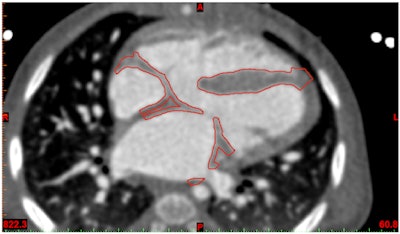

Prior to printing, the accuracy of your final file should be verified against the original DICOM imaging. Did you oversmooth and remove a key feature from the model? Did you cut away a structure that would be an important landmark for the surgeon?

I would recommend a solution that allows the user to overlay the STL surfaces back on the DICOM data. This will allow you to verify accuracy (and convince others of it), as well as make subtle adjustments or refinements to the model.

In addition, it is useful to have a tool that can reconstruct and render your stereolithography (STL) files within the software instead of a simple STL export option. This gives you the advantage of seeing and verifying what you have created prior to 3D printing.